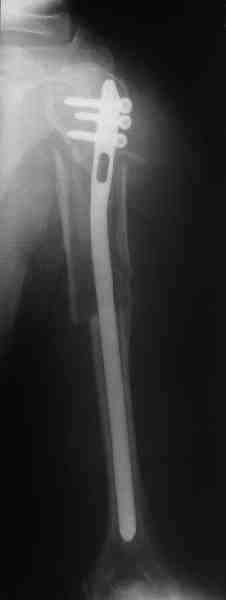

Re: Оскольчатый перелом плеча

Прооперировали больную с переломом плеча все же гвоздем, Фото в приложении.